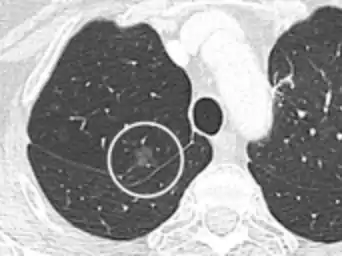

Nodular

There are numerous potential causes of nodular GGOs which can be broadly separated into benign and malignant conditions. Benign conditions potentially leading to the formation of nodular GGOs include aspergillosis, acute eosinophilic pneumonia, focal interstitial fibrosis, granulomatosis with polyangiitis, IgA vasculitis, organizing pneumonia, pulmonary contusion, pulmonary cryptococcus, and thoracic endometriosis. Focal interstitial fibrosis presents a unique challenge when differentiating from malignant nodular GGOs on CT imaging. It is typically persistent over long-term imaging follow-up and shares a similar appearance to malignant nodular GGOs.[9]

Pre-malignant or malignant causes of nodular GGOs include adenocarcinoma, adenocarcinoma in situ, and atypical adenomatous hyperplasia (AAH). One large review study found that 80% of nodular GGOs which were present on repeated CT imaging represented either pre-malignant or malignant growths. Differentiating between pre-malignancy and malignancy on the basis of CT alone can pose a challenge to radiologists; however, there are several features that are indicative of pre-malignant nodules. AAH is a pre-malignant cause of nodular GGO and is more commonly associated with lower attenuation on CT and smaller nodule size (<10 mm) compared to adenocarcinoma.[10] In addition, AAH often lacks the solid features and spiculated appearance that are often associated with malignant growths.[9] In contrast, as adenocarcinoma becomes invasive it will more often cause retraction of adjacent pleura and may show an increase in vascular markings. Nodules >15 mm almost always represent an invasive adenocarcinoma.[9][10]

- CT image showing ground-glass nodule (circled).